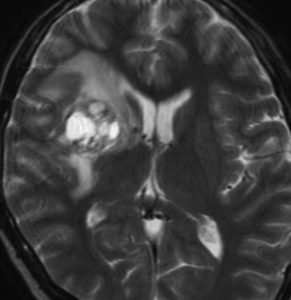

神経下垂体ジャーミノーマと大脳基底核成熟奇形腫

neurophypophyseal germinoma with basal ganglia mature teratoma

12歳の男児が尿崩症で発症しましたが,7ヶ月間診断がつかずに低ナトリウム血症による全身痙攣を生じました。下垂体と右被殻の2箇所に腫瘍があり,AFP 33ng/ml, HCG-beta 1.0mIUと上昇がみられました。神経下垂体の生検術でgerminomaの診断であったために化学療法が開始されました。CPA, VP-16, CDDP, VCRの併用化学療法に,MTXの髄腔内注入が2回でした。なぜこのような乱暴な化学療法を行なったのかは不明です。当然ですが,下垂体のgerminomaは左側のように消失しました。

でも化学療法中に,右大脳基底核にあった腫瘍が増大して,左のMRIのように脳浮腫も悪化しました。この時点で患者さんが転院してきました。腫瘍マーカーは陰転していて,どう見ても奇形腫が化学療法によるparadoxical responseを生じたものでした。ジャーミノーマが消えて奇形腫だけ増大するという現象です。

まず手術で全摘出して,成熟期奇形腫の病理診断を確定しました。それからICE化学療法を2コース加えて,脳脊髄照射 24Gy12分割を行いました。

大脳基底核に胚細胞腫瘍がある場合には全脳照射が基本ですが,なぜ脊髄照射を加えたかということには絶対の根拠はありません。治療前のAFPがやや高く若干の播種性格を有する未熟奇形腫が手術前に消失していたかもしれないという可能性を考えたことと,発症が12歳ですから脊髄照射を24グレイ加えても重篤な遅発性障害が生じないと判断したからです。